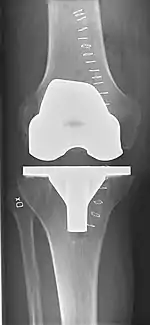

Knee replacement, also known as knee arthroplasty, is a surgical procedure to replace the weight-bearing surfaces of the knee joint to relieve pain and disability, most commonly offered when joint pain is not diminished by conservative sources.[1][2] It may also be performed for other knee diseases, such as rheumatoid arthritis. In patients with severe deformity from advanced rheumatoid arthritis, trauma, or long-standing osteoarthritis, the surgery may be more complicated and carry higher risk. Osteoporosis does not typically cause knee pain, deformity, or inflammation, and is not a reason to perform knee replacement.

Knee replacement surgery can be performed as a partial or a total knee replacement.[3] In general, the surgery consists of replacing the diseased or damaged joint surfaces of the knee with metal and plastic components shaped to allow continued motion of the knee.

Femoral replacement

A round-ended implant is used for the femur, mimicking the natural shape of the joint. On the tibia the component is flat, although it sometimes has a stem that goes down inside the bone for further stability. A flattened or slightly dished high-density polyethylene surface is then inserted onto the tibial component so the weight is transferred metal to plastic, not metal to metal. During the operation any deformities must be corrected, and the ligaments balanced so the knee has a good range of movement, and is stable and aligned. In some cases the articular surface of the patella also is removed and replaced by a polyethylene button cemented to the posterior surface of the patella. In other cases, the patella is replaced unaltered.